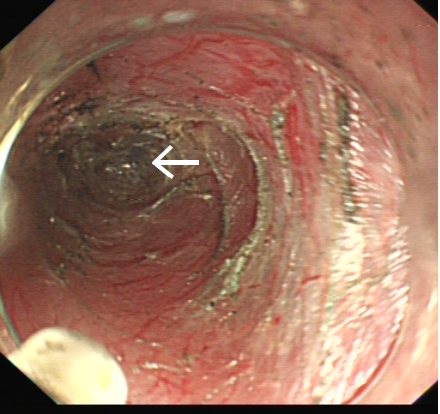

此时已经过去2周,鱼刺刺入的部位已完全愈合,内镜下见到的食管黏膜已十分光滑,未留下任何蛛丝马迹。但鱼骨在体内停留的时间越长,导致消化道穿孔、大动脉破裂出血、难以控制的纵隔和胸腔感染、颈部脓肿致呼吸困难等严重并发症的机率越大,这不仅时刻威胁着患者的生命安全,也给患者带来巨大的心理负担。

但手术远比想像中更为困难,由于解剖结构的因素,内镜在高位食管建立黏膜下隧道本来就有很高难度,还要在狭窄的隧道内完成超声内镜检查,既不能发生食管穿孔,又要准确定位鱼刺,挑战十分严峻。内镜中心多位医生轮番上阵,在护理团队娴熟配合下,经过长达数小时的地毯式搜寻,终于发现鱼刺的踪迹。鉴于已发生过取出过程夹断鱼刺的情况,为保证鱼刺完整,在反复超声探查判断术中引发鱼刺穿破食管的可能性不大后,医生们采用了一种新办法:在鱼刺远端的食管黏膜再切开一道深度接近肌层的小切口,然后自鱼刺近端建好的黏膜下隧道再次进镜,终于将这根长约2.4cm的“流浪”鱼刺完整地从远端的切口里“推赶”了出去。

此次手术是我院首次采用隧道内镜技术完成食管黏膜下异物探查,取出鱼刺的操作在黏膜下层完成,除了近远端两个小切口,隧道表面的黏膜和底部的肌层均保持完整,术后房大姐恢复迅速,隔天就出院回家,恢复正常饮食后无任何不适,全家悬着的心终于落了地。这也是我院首次在消化内镜中心手术间完成气管插管全麻,数小时的手术过程麻醉深度适宜,患者生命征平稳;超声科全程在场提供超声技术支持,为手术的成功提供了有力保障。据文献检索,目前国内外尚无采用近远端双切口顺行推送取出食管黏膜下异物的报道。